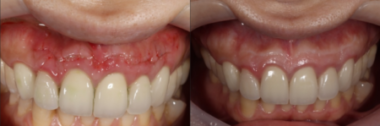

術後およそ2週間で、患者様が訴えていた違和感は大きく改善されました。

その後も3ヶ月、1年と経過を追って確認した結果、現在に至るまで外科手術による瘢痕はほとんど見られず、

美しい歯茎のラインを維持したまま、無事に治療を完了することができました。

画像がこちらになります。

今回の患者様は②の「歯根端切除術」を選択され、無事に根尖性歯周炎が治癒しました。

また、心配されていた審美的な問題もなく、自然な見た目を保ったまま治療を終えることができました。